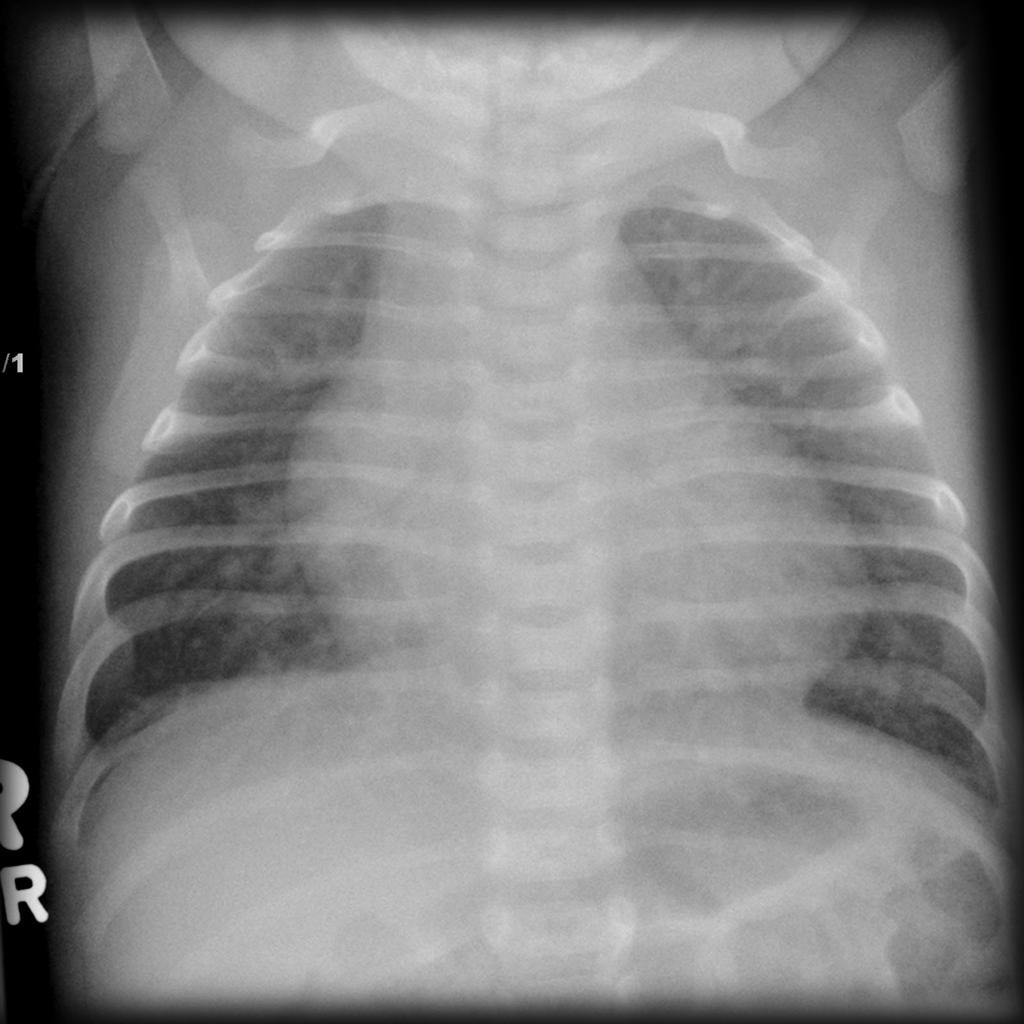

- Chest radiography

- Infants

- Cardiomegaly with increased pulmonary vascular markings

- Older children and adults

- Rib notching from large collateral development

- “3” sign from indentation of aortic wall at coarctation site